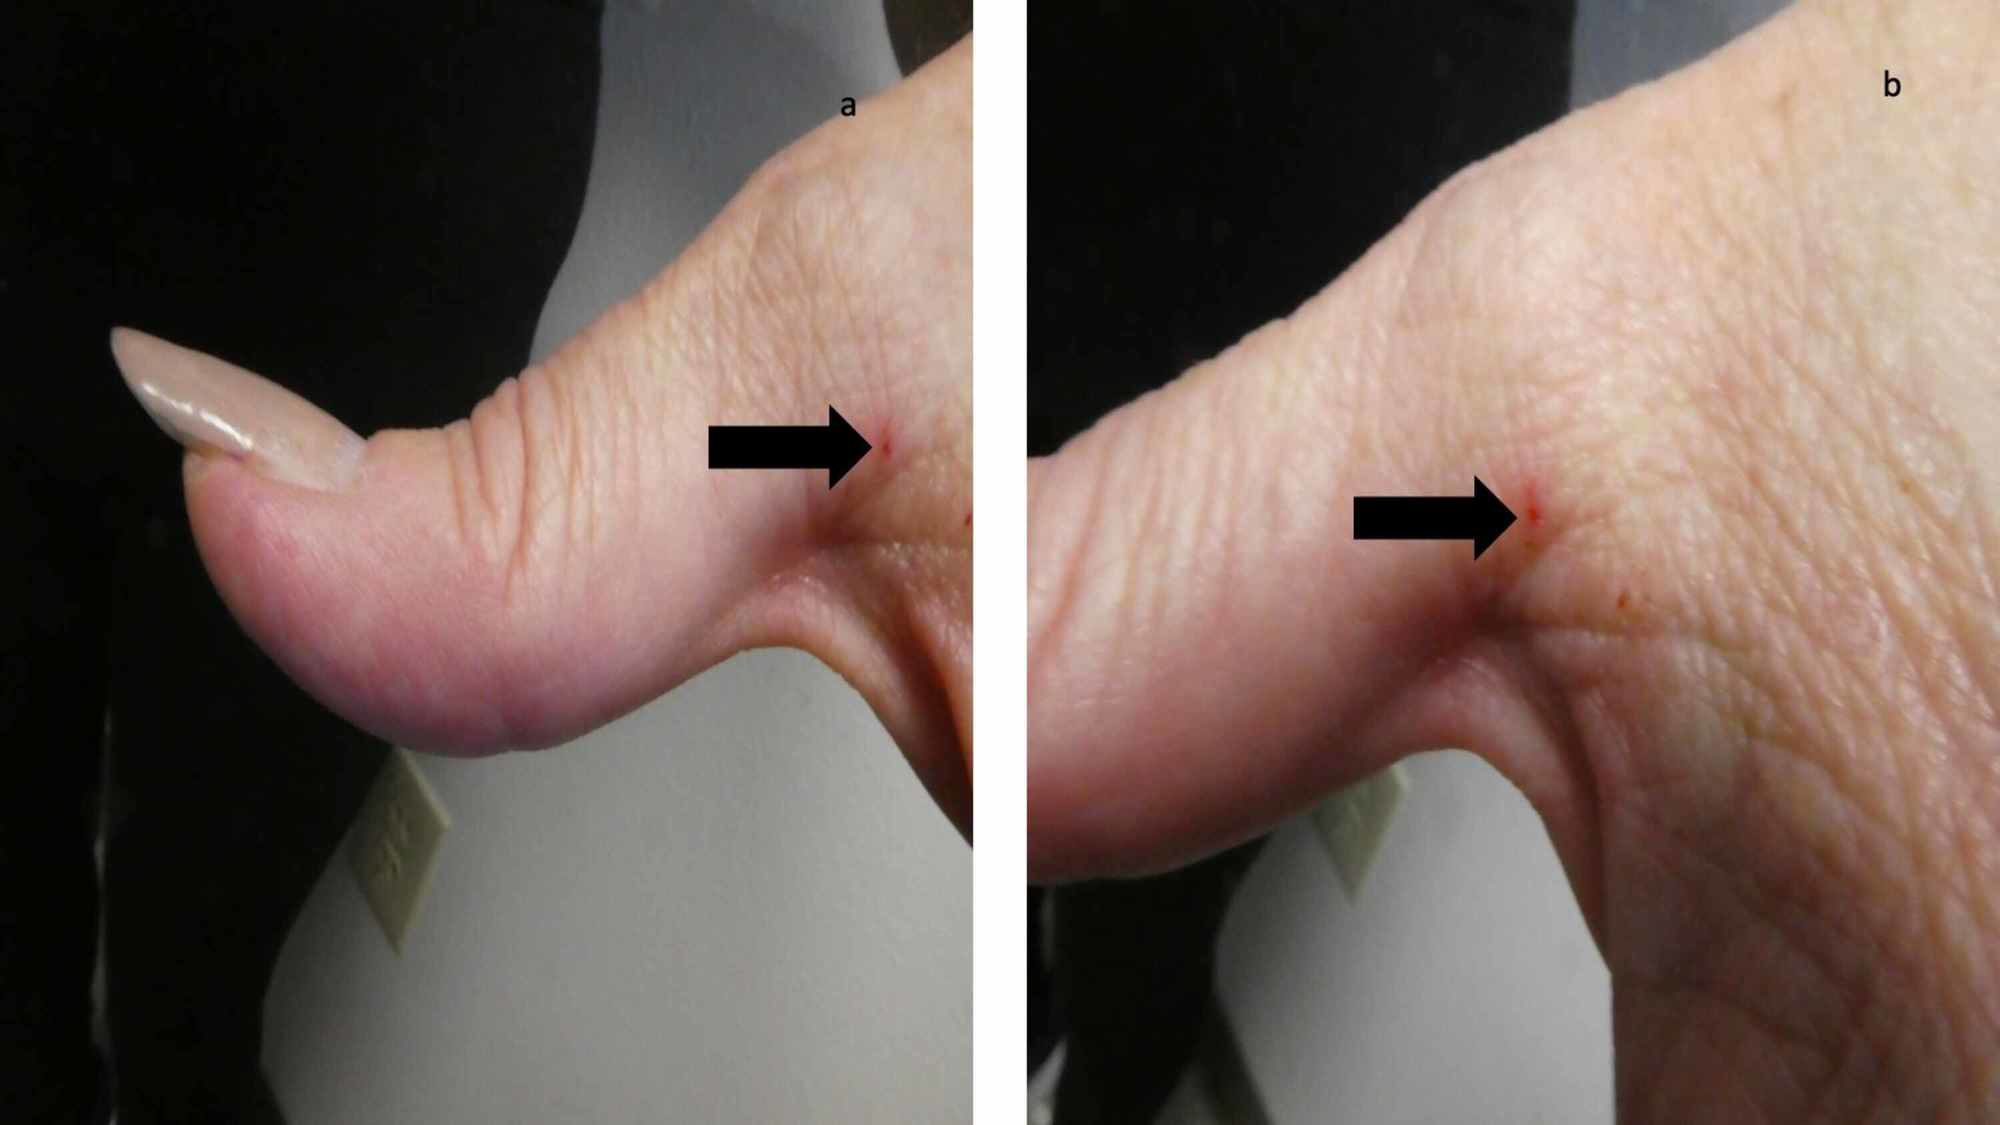

SCABİES (UYUZ)

Uyuz; Sarcoptes scabiei var. Hominis adı verilen akarın (böcek) sebep olduğu tüm dünyada yaygın olarak görülen bir hastalıktır.

Uyuz böceği deride tüneller açarak bu tünellerin içinde yaşar.

İlk defa uyuza yakalanan bir kişide belirtilerin başlaması 2-6 hafta kadar sürebilir. Ancak daha önce uyuza yakalanan bir kişide, belirtiler genellikle maruz kaldıktan 1-4 gün içinde ortaya çıkar. Hastalık belirtilerinin başlamadığı bu dönemlerde bile kişi uyuzu başkalarına bulaştırabilir.

Uyuzun en önemli belirtisi şiddetli gece kaşıntısıdır. Kaşıntı, kişinin yatağa girip ısınması ile artar ve kişiyi uykudan uyandırabilecek şiddette iken gündüzleri daha hafiftir. Kaşıntı genellikle el parmak araları, el bileğinin iç yüzü, bilekler, koltuk altları, dirsekler ve kasıklarda görülmekle birlikte tüm vücutta görülebilmektedir. Hastalığın en belirgin bulgusu parmaklar arasında dalgalı kirli bir çizgi halinde görülen, uyuz böceğinin içinde yaşadığı, gri beyaz renkli, 1-10 mm uzunluğundaki tünellerdir. Kişilerde özellikle geceleri artan şiddetli kaşıntı ve deride görülen içi su dolu keseciklerin görülmesi uyuz şüphesini arttırır.

CloseSCABİES (UYUZ)

Uyuz; Sarcoptes scabiei var. Hominis adı verilen akarın (böcek) sebep olduğu tüm dünyada yaygın olarak görülen bir hastalıktır.

Uyuz böceği deride tüneller açarak bu tünellerin içinde yaşar.

İlk defa uyuza yakalanan bir kişide belirtilerin başlaması 2-6 hafta kadar sürebilir. Ancak daha önce uyuza yakalanan bir kişide, belirtiler genellikle maruz kaldıktan 1-4 gün içinde ortaya çıkar. Hastalık belirtilerinin başlamadığı bu dönemlerde bile kişi uyuzu başkalarına bulaştırabilir.Uyuzun en önemli belirtisi şiddetli gece kaşıntısıdır. Kaşıntı, kişinin yatağa girip ısınması ile artar ve kişiyi uykudan uyandırabilecek şiddette iken gündüzleri daha hafiftir. Kaşıntı genellikle el parmak araları, el bileğinin iç yüzü, bilekler, koltuk altları, dirsekler ve kasıklarda görülmekle birlikte tüm vücutta görülebilmektedir. Hastalığın en belirgin bulgusu parmaklar arasında dalgalı kirli bir çizgi halinde görülen, uyuz böceğinin içinde yaşadığı, gri beyaz renkli, 1-10 mm uzunluğundaki tünellerdir. Kişilerde özellikle geceleri artan şiddetli kaşıntı ve deride görülen içi su dolu keseciklerin görülmesi uyuz şüphesini arttırır.